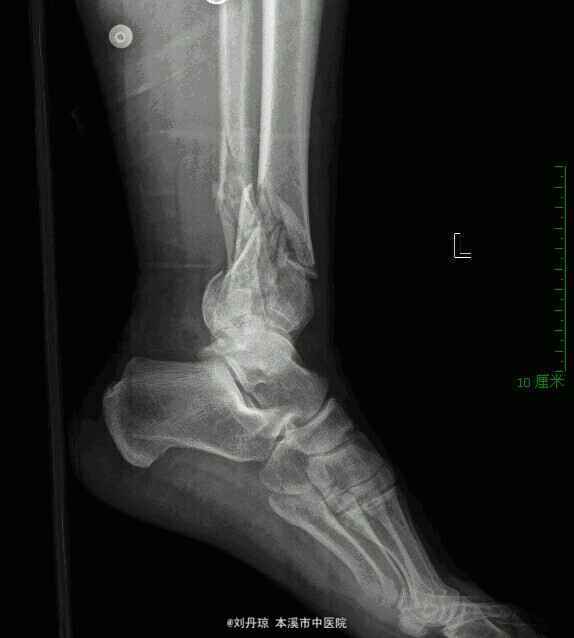

患者男性51岁左踝外伤后刺痛、肿胀、活动受限2小时。病史:患者2小时前从10米高处坠落,左踝摔伤,伤后来诊,门诊医师以左踝pilon骨折诊断收入院。

左踝关节粉碎骨折,左踝pilon骨折。